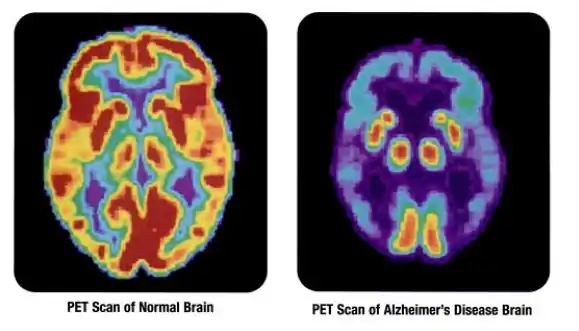

Fluorine biology is also relevant to a number of cutting-edge technologies. PFCs (perfluorocarbons) are capable of holding enough oxygen to support human liquid breathing. Organofluorine in the form of its radioisotope 18F is also at the heart of a modern medical imaging technique known as positron emission tomography (PET). A PET scan produces three-dimensional colored images of parts of the body that use a lot of sugar, particularly the brain or tumors.

Compounds containing fluorine-18, a radioactive isotope that emits positrons, are often used in positron emission tomography (PET) scanning, because the isotope's half-life of about 110 minutes is usefully long by positron-emitter standards. One such radiopharmaceutical is 2-deoxy-2-(18F)fluoro-D-glucose (generically referred to as fludeoxyglucose), commonly abbreviated as 18F-FDG, or simply FDG.[22] In PET imaging, FDG can be used for assessing glucose metabolism in the brain and for imaging cancer tumors. After injection into the blood, FDG is taken up by "FDG-avid" tissues with a high need for glucose, such as the brain and most types of malignant tumors.[23] Tomography, often assisted by a computer to form a PET/CT (CT stands for "computer tomography") machine, can then be used to diagnose or monitor treatment of cancers, especially Hodgkin's lymphoma, lung cancer, and breast cancer.[24]